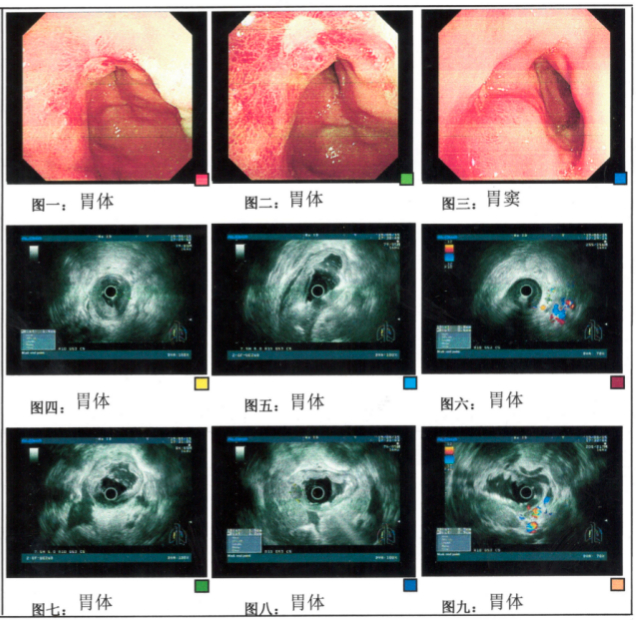

用药2周期后,于2023年4月8日复查腹部CT检查(图3),提示胃壁增厚僵硬,以胃体为著,较前好转,考虑胃癌(T4N+);于2023年4月15日复查纤维胃镜检查(图4),提示胃体小弯低回声浸润性病变(T4N3)侵及胃窦,镜下见病灶较前改善,超声表现无明显变化。

用药2周期后,于2023年6月17日复查腹部CT检查(图5),提示胃壁增厚僵硬,以胃体为著,较前略减轻,考虑胃癌(T3N1);于2023年6月24日复查纤维胃镜检查(图6),提示胃体小弯低回声浸润性病变(T3N1)侵及胃窦。